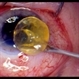

- anterior segment, cataract surgery

- Narciso F. Atienza, Jr. MD, MBA

- Photo slit lamp biomicroscope

- 57-year-old male patient who underwent phacoemulsification. Pre-op vision was 20/70. Complicated surgery. With vitreous loSS, cataract surgeon decided to place the foldable intraocular lens in the AC. Presented in the clinic with a vision of hand movement, with intra-ocular preSSure of 65 mmHg. He was managed by the same surgeon who gave Cosopt TID, and Alphagan QID.